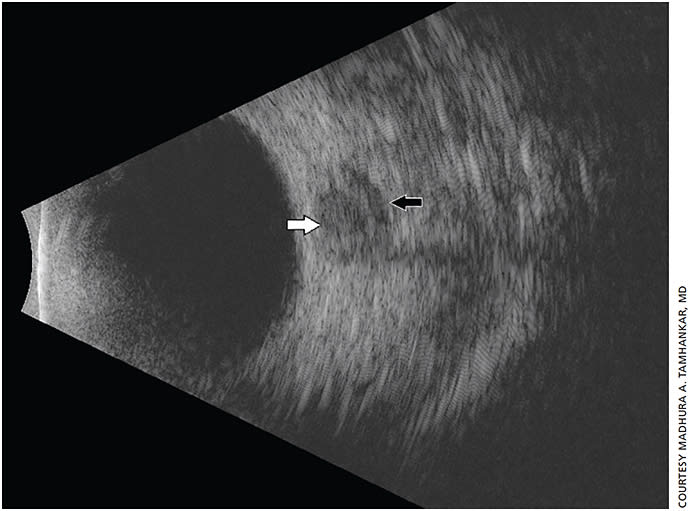

In true papilledema, increased intracranial pressure (ICP) is transmitted along the subdural space within the optic nerve. Using B-scan ultrasonography, one can detect a widening of the optic nerve sheath diameter due to the presence of increased fluid within the nerve sheath. This can indicate true papilledema (Figure 2). Studies have shown high levels of correlation between optic nerve sheath width by ultrasonography and ICP measured directly through invasive monitors.5

Figure 2. Cross sectional B-scan showing optic nerve in cross section (white arrow) and distended nerve sheath fluid (black arrow).